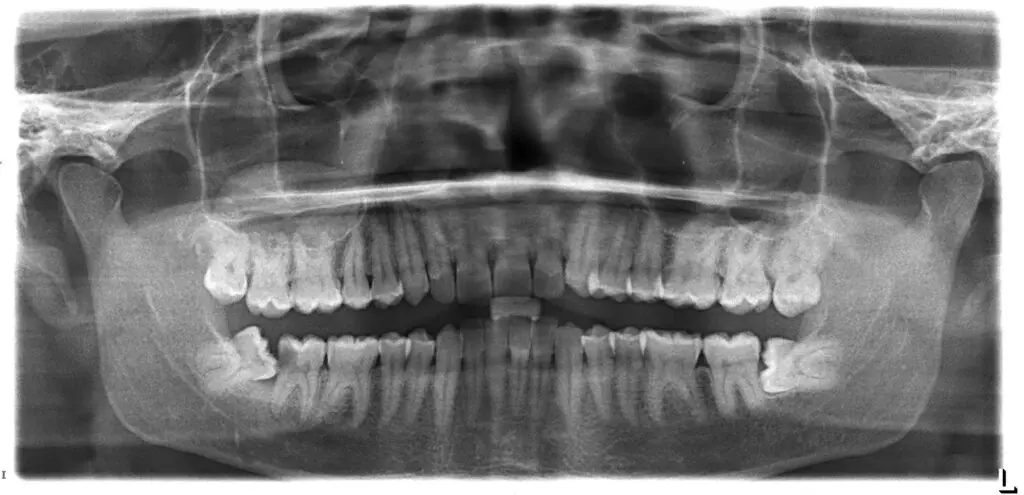

Correctly diagnosing dental problems including decay or periodontal disease

Quite often, decay develops in areas of the mouth that may not be clinically visible. This includes areas between the teeth or under existing restorations. X-Rays are able to detect such problems before it progresses to an advanced stage. Problems such as cavities, cysts, abscesses, and the progress of dental development of young children can be assessed. Dental X-rays can reveal:

Produces a superior X-Ray image quality for better diagnosis.